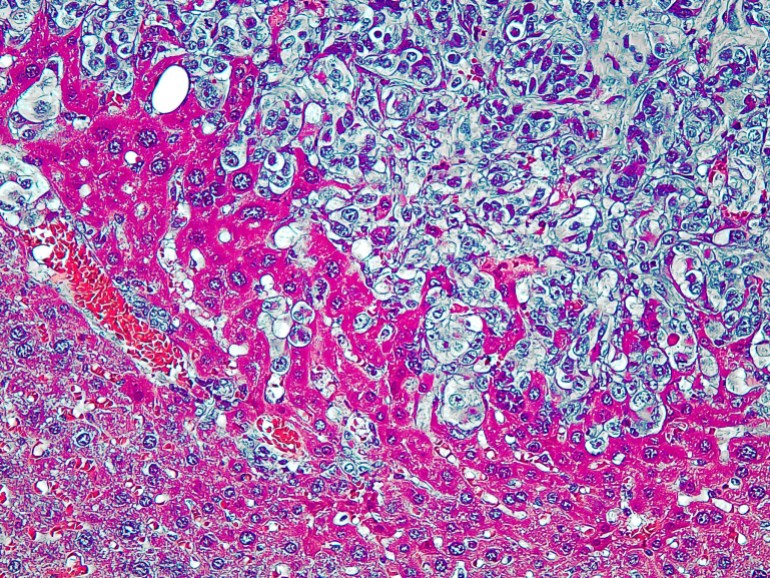

ولمعرفة النظائر المميزة للخلايا السرطانية، زرع الفريق البحثي خلايا الخميرة وخلايا كبد الفئران في المختبر، ثم حللوا ذرات الهيدروجين الخاصة بهما، ووجد الفريق أن الخلايا التي تنمو بسرعة كبيرة مثل خلايا الخميرة، تحتوي على نسبة مختلفة كثيرا من ذرات الهيدروجين مقابل ذرات “الديوتيريوم”، وهو ما جعلهم يفترضون أنهم سيجدون نفس البصمة الذرية في الخلايا السرطانية التي تنمو هي الأخرى سريعا.

وبناء على تحليلهم، لاحظ الباحثون اختلافات كبيرة في نسب نظائر الهيدروجين بين الأنواع المختلفة من الخلايا، إذ أظهرت الخلايا السرطانية التي تنمو بسرعة، تركيبة مميزة مقارنة بالخلايا السليمة.

وكانت البصمة الهيدروجينية المميزة للخلايا السرطانية هي وجود عدد أقل من ذرات “الديوتيريوم” مقارنة بالخلايا الطبيعية، واحتوت الخلايا السرطانية وخلايا الخميرة سريعة النمو التي تحاكي النمو السرطاني، على ذرات “ديوتيريوم” أقل بنسبة 50٪ تقريبا في المتوسط مقارنة بالخلايا السليمة.